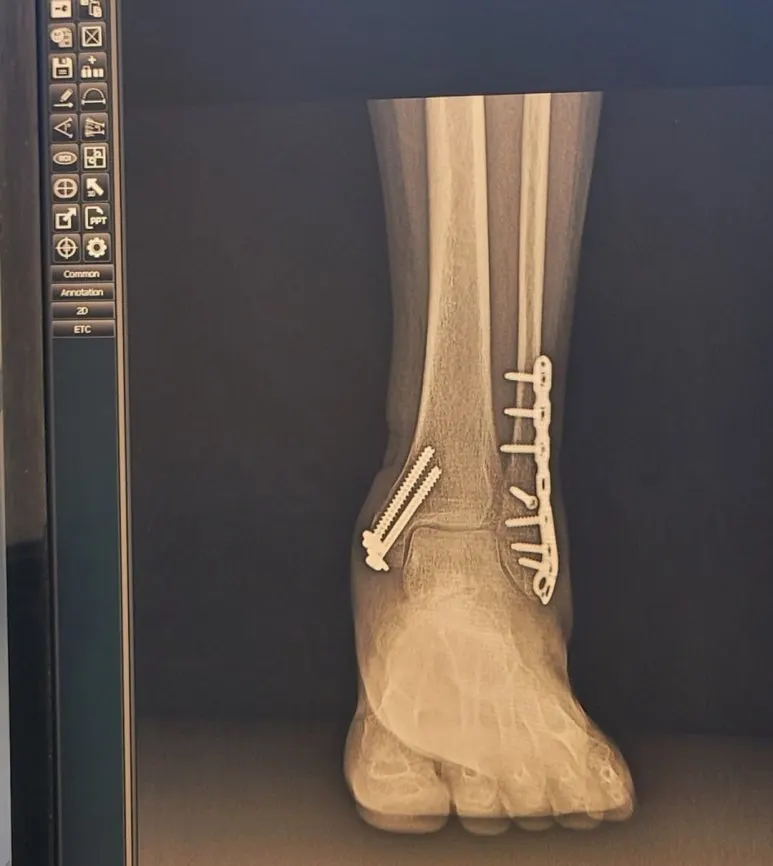

러닝 할 때마다 보스턴 응원의 환성이 와아~들리는 듯해요. 마지막 10번 뉴스는 재활 러닝입니다. 2024 5월 발목 골절과 수술, 재활은 아주 힘겨웠답니다. 수술 당일 통증은 아직도 생생해서 고개가 절레절레 흔들어집니다.

KakaoTalk_20240915_141551685.jpg?type=w773

KakaoTalk_20240915_190726165.jpg?type=w773 발목 골절 수술, 재활 걷기, 조깅

재활 과정에서 뭘 할 수 있을까 고민했고 독서와 글쓰기와 근력 키우기로 시간을 보내기로 했어요. 불편했지만 잘 보낸 것 같아요.

걷기 재활, 1분 뛰기 재활로 시작해서 10km를 뛸 수 있어서 아주 행복한 재활 과정이었어요.

내년 6월 철심 제거 수술 후에는 2025년 춘천 마라톤 풀코스에 도전하고 싶어요.